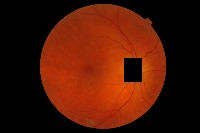

hard-exudate-detection1 Computer Vision Project

Diabetes Retinopathy Diagnosis: Medical professionals could use hard-exudate-detection1 to identify diabetic retinopathy in patients during routine screenings or for diagnosing symptoms, as hard exudates are a typical sign of this medical condition.

Automated Retinal Image Analysis: The identification of hard exudates could provide crucial information for automatic retinal image analysis software. It would provide an extra tool for detailed assessment of retinal images, providing comprehensive and accurate results.